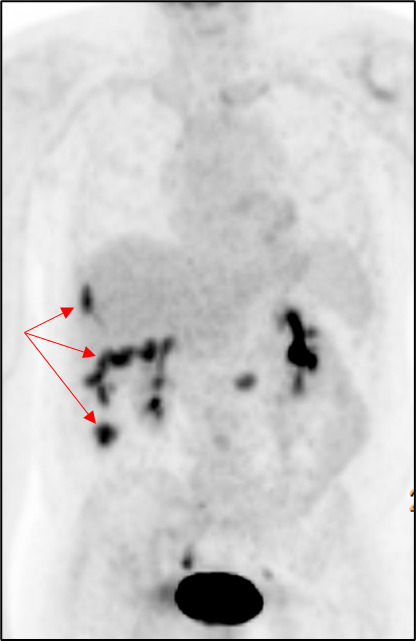

A computer tomography (CT) scan of the abdomen and pelvis was performed and showed nodularity along the right hemidiaphragm, soft tissue nodularity within the peritoneum, nodular soft tissue along inferior mesenteric and superior rectal distribution, and indistinct areas of enhancement deep to right ventral abdominal wall concerning for peritoneal metastases (Figure 2). A positron emission tomography (PET) scan showed multifocal FDG-avid peritoneal lesions suspicious of metastatic disease of uncertain primary origin (Figure 3). Image-guided biopsies (CT- and ultrasound-guided) from the right upper and lower quadrants revealed only fibroinflammatory tissue, with negative microbiologic and cytologic results. Tumor markers (CA19-9, CA125, AFP, CEA, β-hCG) were within normal limits.

Radiologically, these lesions often appear as heterogeneous soft-tissue masses or rim-enhancing collections that can be mistaken for malignancy.9 The presence of small, calcified foci within lesions may suggest gallstones; however, radiolucent stones can be missed, complicating diagnosis. PET scanning can further mislead clinicians by showing FDG uptake in inflammatory tissue, as occurred in this case, prompting extensive workup for cancer of unknown primary.